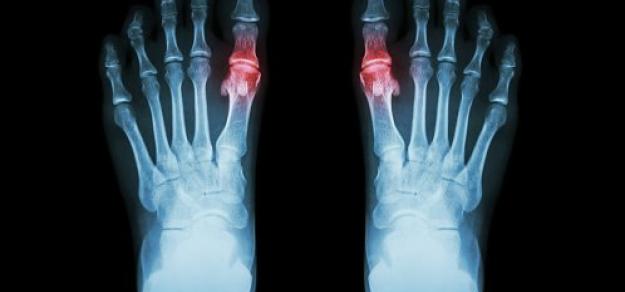

Asociación de enfermedad renal crónica con el uso de alopurinol en el tratamiento de la gota

JAMA Intern Med, 8 de octubre de 2018. En este estudio de cohorte de base poblacional del Reino Unido , el uso de alopurinol en pacientes con gota no aumentó el riesgo de disminución de la función renal, y se asoció significativamente con un riesgo 13% menor a dosis de 300 mg o más por día. Lo que significa que el alopurinol no parece estar asociado con una disminución de la función renal, y los médicos deben considerar otros contribuyentes potenciales cuando se enfrentan a una disminución de la función renal en pacientes con gota.